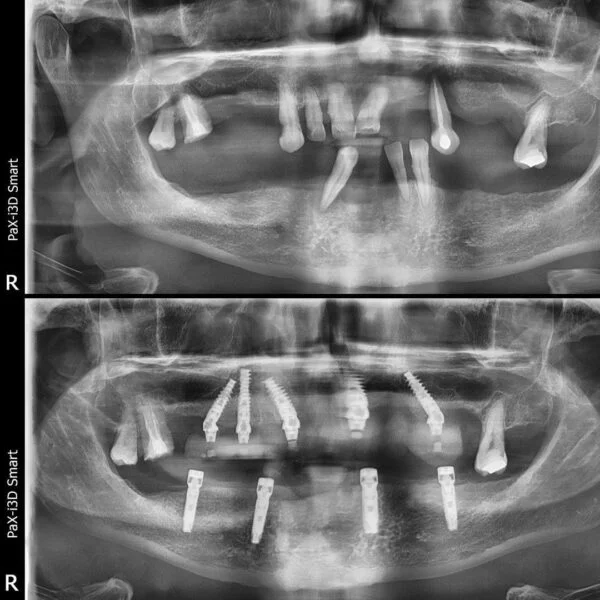

Implantul dentar este adesea recomandat deoarece prezintă foarte multe avantaje, iar, de multe ori, este unica soluție pentru protezarea unei edentații.